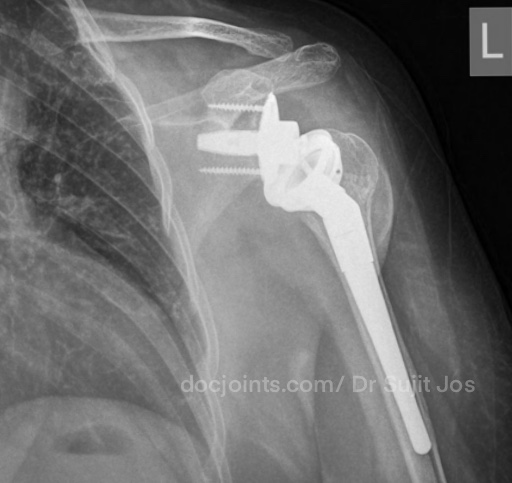

On presentation to the OP, the lifting power of the shoulder was significantly affected on strength testing (emply can test indicating supraspinatus tendon tear) and outward rotation was very weak (indicating Infraspinatus tendon tear). Xray and MRI images attached below.

There was significant fatty infiltration of the rotator cuff muscles along with osteoarthritis of the shoulder joint. Treatment options were discussed. Reverse shoulder arthroplasty is the modern treatment for this type of pathology, which can restore muscle function by orienting the shoulder centre of rotation in such a way that the Deltoid muscle can help in elevating the limb from neutral position (Read more about Reverse shoulder replacement >>).